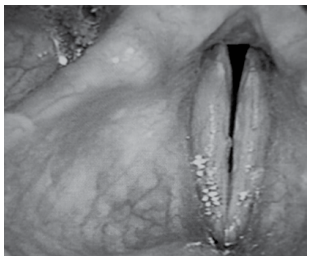

Avalie cuidadosamente, a seguir, a imagem de uma paciente de 41 anos com disfonia funcional.

(Mara Behlau, Voz: o livro do especialista)

A figura é compatível com uma fenda

(Mara Behlau, Voz: o livro do especialista)

A figura é compatível com uma fenda